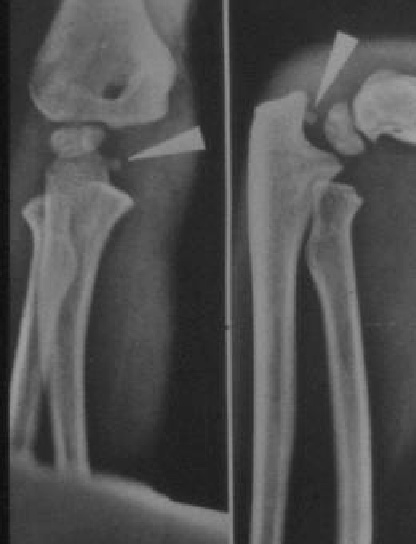

• a fracture of the medial epicondyle of the elbow that is the third most common fracture seen in children and is usually seen in boys between the age of 9 and 14.

• associated with elbow dislocations in approximately 50-60% of cases q

• most spontaneously reduce but fragment remains incarcerated in joint in ~ 15% of cases

• displacement is difficult to measure accurately as medial epicondyle is located on the posteromedial aspect of the distal humerus and fragment displaces anteriorly

• internal oblique view to evaluate displacement

• distal humeral axial view

• may also improve accuracy of measuring displacement

• obtained by angling beam 25 degrees anterior to long axis of humerus